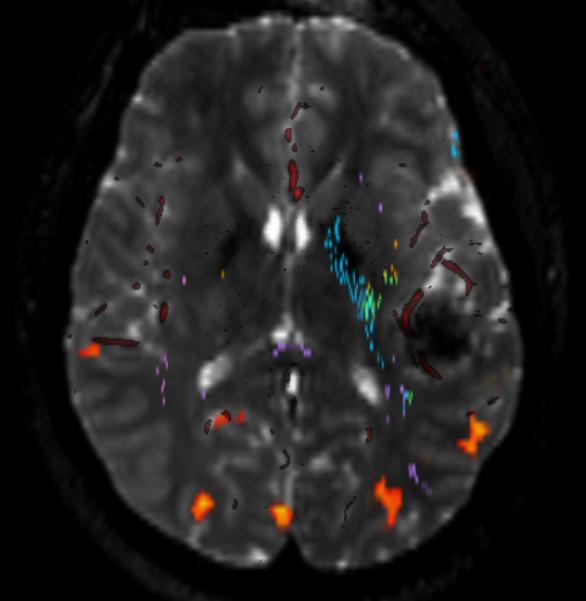

Dynamic Susceptibility Contrast MRI Perfusion image A for Radiology

How it works: Dynamic Susceptibility Contrast or DSC is a method of measuring cerebral blood flow, or blood flow to the brain. The technique requires intravenous contrast delivered through an automated power injector attached to an IV. The scanner creates an image showing multiple cerebral perfusion parameters including cerebral blood flow, mean time to enhance, and negative enhancement integral or cerebral blood volume. These techniques are most beneficial to patients with vascular stenosis, stroke, and brain tumors.

Equipment: Our MRI suite uses the latest Phillips 3.0 tesla magnets coupled with a state of the art Phillips Clinical Cerebral perfusion software package. Processing is performed by the technologist as soon as the scan is completed and images are available for immediate interpretation.

Dynamic Susceptibility Contrast MRI Perfusion image B for Radiology

Benefits: DSC perfusion gives the most thorough evaluation of cerebral blood flow. In addition to flow, the technique gives other parameters such as blood volume and transit time that allow the neuroradiologist to more accurately depict the true state of the brain perfusion. These additional parameters have been thoroughly studied with regard to stroke and tumor evaluation.1

Stroke and TIA: The perfusion parameters can show brain tissue at risk of stroke before the stroke has occurred. The best example of this is a patient with a transient ischemic attack or TIA . These patient's have brief stroke like symptoms and but may have a normal MRI. DSC perfusion can reveal subtle perfusion changes that could allow possible therapeutic interventions to prevent a future stroke.

Tumors: Cerebral blood volume correlates with the tumor grade or how malignant the tumor is. Brain tumors are frequently heterogeneous when looked at under the microscope. Perfusion can help guide the neurosurgeon to obtain the most accurate biopsy sample of the tumor to optimize therapy after surgery. Perfusion can also help distinguish a brain metastasis, primary brain tumors, and an infectious process prior to surgery.

Exam Preparation: The technologist will interview you prior to scan to make sure you have no contraindications to being in the MRI scanner. Patients with braces or other metal near the head or neck may not be suitable for DSC because of the artifacts the metal can cause. Patients who have kidney problems may not be able to get MRI contrast without being consented by a radiologist. If you think you have problems with your kidneys please let the technologist and scheduler know. Blood lab values may be obtained prior to the MRI scan to determine if you can receive MRI contrast safely. Patients will be given an IV prior to entering the MRI scanner.

What to expect: DSC perfusion alone takes approximately 2 minutes of scanner time. While the contrast is being injected, the scanner is dynamically acquiring images through the brain. It is very important to remain very still during this portion of the examination. The study is done in conjunction with routine anatomic imaging.

Content by Dr. Jeffrey Pollock